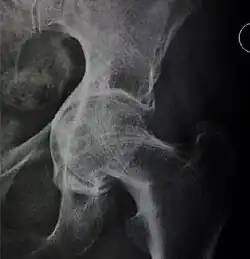

![Figure 5 (c). Protrusio acetabuli.[3]](./_assets_/X-ray_of_protrusio_acetabuli.jpg)